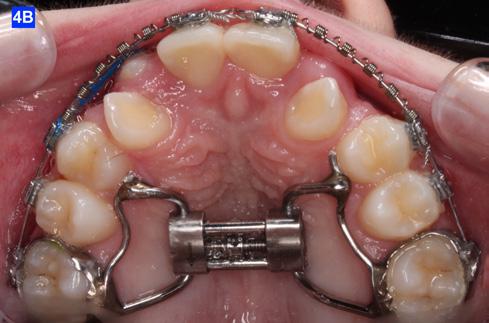

following completion of the treatment. Composite add-ons were considered on maxillary lateral incisors, if required (Figure 3-A, B, C).

The maxillary cuspids were erupting mesially to the lateral incisors, with very little space to accommodate both teeth without an odontectomy. The expansion was continued (1/4 turn 2x per week), and an attempt was made to create more space for erupting cuspids with an open coil spring (OCS) – between the central incisors and the cuspids (Molar distalization spring, a .010 x .045 - Ortho Organizers). The OCS was measured and cut 4.0 mm longer than the available space. The maxillary arch wire was a .018 SS. An elastomeric chain (EC) was attached from the Hyrax to the lingual button on the lateral incisors. It was necessary to first pull the lateral incisors away from the alveolar process to prevent the break down of the buccal cortical bone around the cuspids (Figure

4-A, Figure 3A: The patient transferred to our office, frontal view Figure 3B: The patient transferred to our office, maxilla, occlusal view Figure 3C: The patient transferred to our office, mandible, occlusal view Figure 4A: OCS, frontal view Figure 4B: Hyrax, occlusal view Figure 4C: Retraction of maxillary lateral incisors